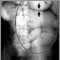

Ileus - X-ray of bowel distension